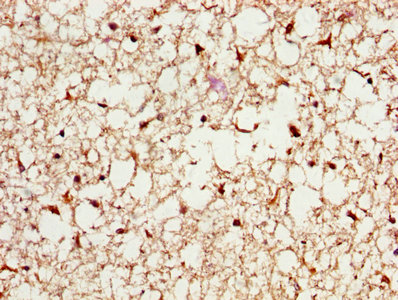

IHC image of CSB-PA13674A0Rb diluted at 1:200 and staining in paraffin-embedded human brain tissue performed on a Leica BondTM system. After dewaxing and hydration, antigen retrieval was mediated by high pressure in a citrate buffer (pH 6.0). Section was blocked with 10% normal goat serum 30min at RT. Then primary antibody (1% BSA) was incubated at 4°C overnight. The primary is detected by a biotinylated secondary antibody and visualized using an HRP conjugated SP system.